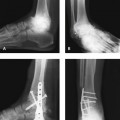

The triad of recurrent ankle sprains, heel varus, and stress fracture of the fifth metatarsal should always be taken into consideration when treatment is planned in the sedentary or athletic patient (Figure 31-1). The case illustrated in Figure 31-1 represents a good example of failure of treatment if the underlying biomechanical and anatomic process is ignored. A calcaneus osteotomy, in addition to a stronger ankle ligament repair, which might have prevented the subsequent problems, would have provided improved correction. An ankle ligament reconstruction can be performed without correcting the heel varus, but the outcome will depend on the flexibility of the subtalar joint and presence of additional symptoms.